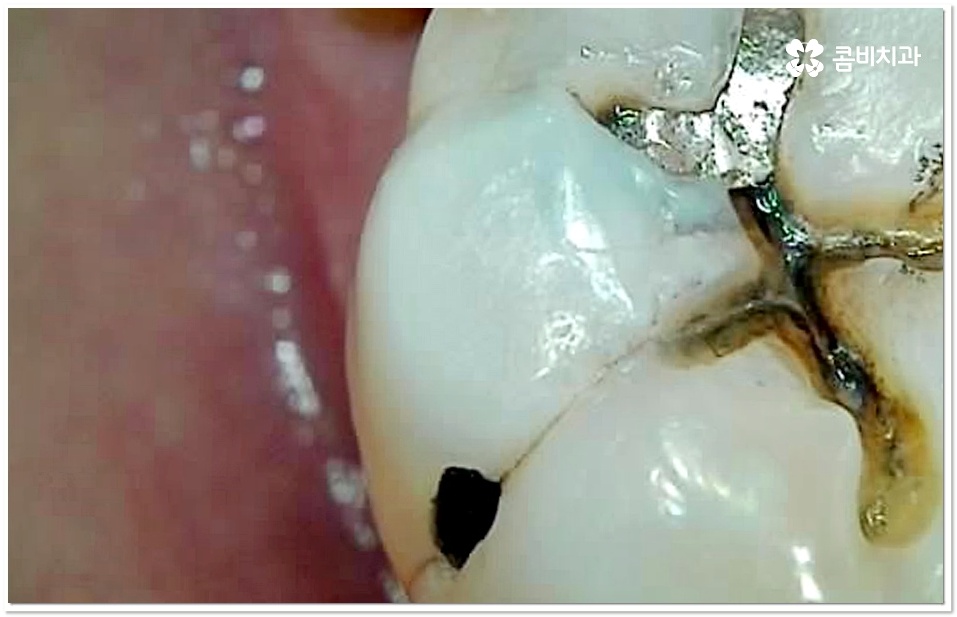

충치 초기에는 손상이 크지 않고 대부분 겉면인 법랑질에 국한되는 경우가 많아 해당 부위를 깨끗하게 삭제한 후 레진으로 직접 때우는 방법을 통해 보다 빠르고 간편한 수복을 할 수 있어요. 그러나 충치가 더 진행되면 손상 부위가 넓고 깊어지기 때문에 레진 처치는 적합하지 않으므로 인레이나 온레이와 같이 보철물을 만들어 끼워주는 방법을 이용하고 있는데요. 특히 어금니는 씹는 힘을 많이 받는 치아이기 때문에 보통 인레이와 같이 내구성이 더 높은 어금니 충치치료 방법을 많이 쓰고 있어요.

충치 초기라고 하더라도 만약 저작면이 아닌 인접면 충치가 생긴 경우에는 상황에 따라 레진 치료가 아닌 인레이 어금니 충치치료 방법을 쓸 수 있는데요. 이때 치아 옆면을 재건해야 하는 경우처럼 까다로운 케이스에 있어서는 더욱 세심한 주의력과 숙련된 노하우가 필요할 거예요.

특히 20살 전후로는 사랑니 때문에 인접면 충치가 자주 발생할 수 있으니 신경써 주시길 권유드리고 있는데요. 어금니 뒤쪽으로 사랑니가 나올 때 비정상적으로 맹출이 되어 비스듬한 각도로 어금니와의 사이에 좁은 틈새를 만들게 되면 음식물 찌꺼기가 잘 끼고 쉽게 빠지지 않아 더욱 충치나 잇몸 염증이 유발되기 쉬우니 신경써서 관리해 주시길 바라고 있어요.